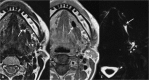

Inflammatory and obstructive disorders of the salivary glands are caused by very different pathological conditions affecting the gland tissue and/or the excretory system. The clinical setting is essential to address the appropriate diagnostic imaging work-up. According to history and physical examination, four main clinical scenarios can be recognised: (1) acute generalised swelling of major salivary glands; (2) acute swelling of a single major salivary gland; (3) chronic generalised swelling of major salivary glands, associated or not with "dry mouth"; (4) chronic or prolonged swelling of a single major salivary gland. The algorithm for imaging salivary glands depends on the scenario with which the patient presents to the clinician. Imaging is essential to confirm clinical diagnosis, define the extent of the disease and identify complications. Imaging techniques include ultrasound (US), computed tomography (CT) and magnetic resonance (MR) with MR sialography.